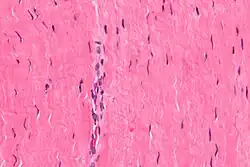

V hustém vazivu převažuje vláknitá hmota kolagenních vláken[4] nad množstvím volných buněk a amorfní buněčné hmoty,[5] fixními buňkami jsou drobné polygonální fibrocyty zasahující svými výběžky mezi kolagenní vlákna, ojediněle i mezi elastická vlákna.[2] Je méně ohebné, zato daleko více odolává mechanickým stresům.[4] Podle uspořádání kolagenních vláken se husté vazivo dělí na dva typy:

Diferencuje se v místech, kde převažuje tah v různých směrech. Kolagenní vlákna se mezi sebou plsťovitě[2] proplétají, fibrocytů je jen minimum a jsou zatlačeny do pozadí[3] mezi svazky vláken.[2]

Vytváří se tam, kde na kolagenní vlákna působí tah pouze v jednom směru. Skládá se z paralelně seřazených kolagenních vláken vytvářejících snopce, mezi kterými jsou sloupovitě za sebou vmezeřeny fibroblasty.[3]

Kolagen je eosinofilní, barví se kyselými barvivy, např. eosinem, anilinovou modří, světlou zelení, AZANem, pikrofuchsinem (van Giesonovo barvivo, Weingert van Giesonova metoda) nebo šafránem.